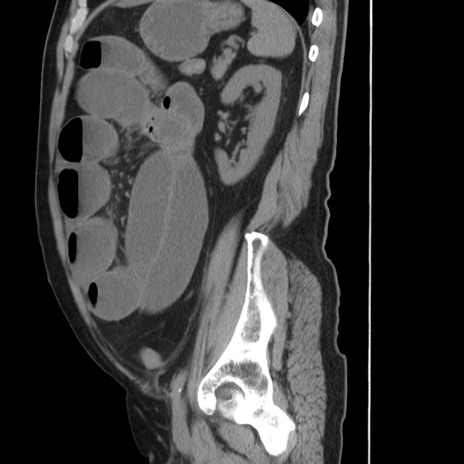

症例20(矢状断像)

【症例】 60歳代男性

【主訴】 腹部膨満、嘔吐

【現病歴】5日前頃より倦怠感を認め食事量減少し4日前の朝嘔吐、食事摂取困難となった。 3日前近医受診し点滴施行され整腸剤などを処方された。 当日他院を受診し、腹部膨満著明、炎症反応の上昇(CRP10.8、WBC11200)あり、紹介受診となる。

【身体所見】 意識JCS1 受け答えがはっきりしないBP 111/57mHg、 P 67bpm、、BT35.2°C、SpO2 97%(RA)、 腹部:膨隆、打診で鼓音あり、全体的に圧痛有り、腸蠕動音(-)、反跳痛ははっきりせず。

【データ】WBC 11400、CRP 14.20